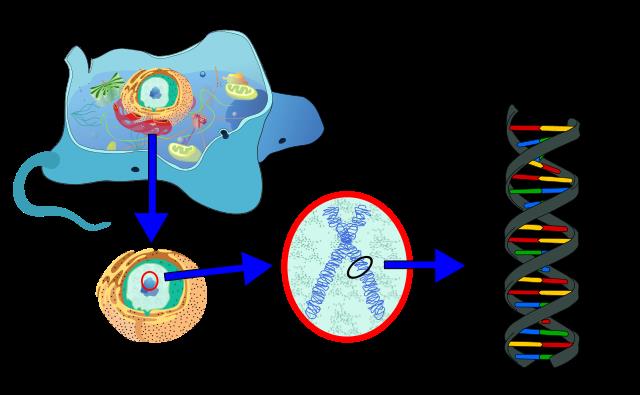

DNA

DNA یا دئوکسی ریبونوکلئیک اسید نوعی ماده در بدن تمام موجودات زنده است که دستورالعمل های ژنتیکی را حمل میکند.

این مولکول بزرگ دستورالعمل های ساخت مواد لازم بدن از قبیل ساخت پروتئین و سایر مواد لازم را با خود حمل کرده و باعث انتقال اطلاعات ژنتیکی از والدین به فرزندان میشود.